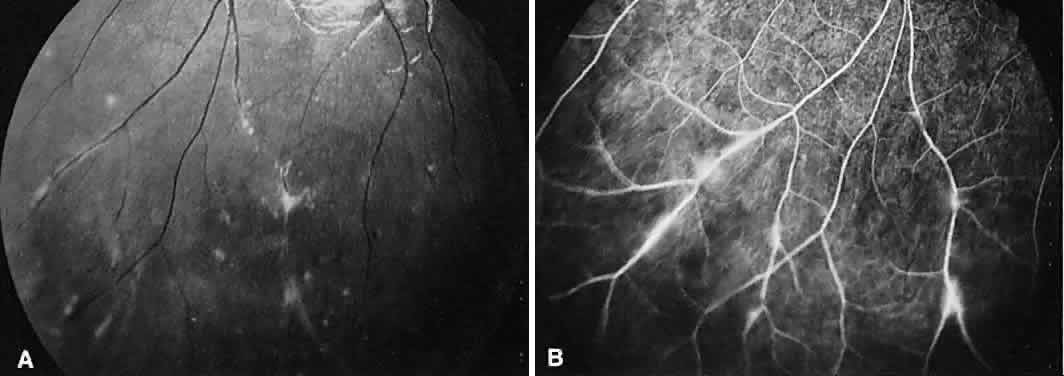

On fluorescein angiography, there is venular wall staining (Fig. 9),30 hyperfluorescence, and leakage of the peripheral inflammatory membranes.31 Cystoid macular edema often is evident.30 Optic disc, peripheral retinal, and subretinal32–34 neovascularization are rare.

Fig. 9. Intermediate uveitis. A. Red-free photography of the peripheral retina shows sheathing of the retinal venules. B. Fluorescein angiography shows staining of the vessel walls with leakage from the peripheral venules.